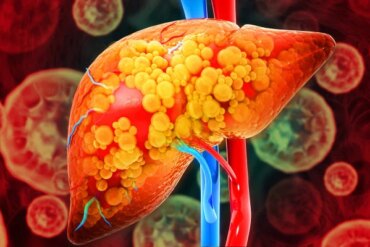

Gordura no fígado: entenda as causas da doença em pessoas magras

A obesidade é um dos principais fatores de risco para o diagnóstico de esteatose hepática, doença conhecida como gordura no fígado. Mas isso não significa...